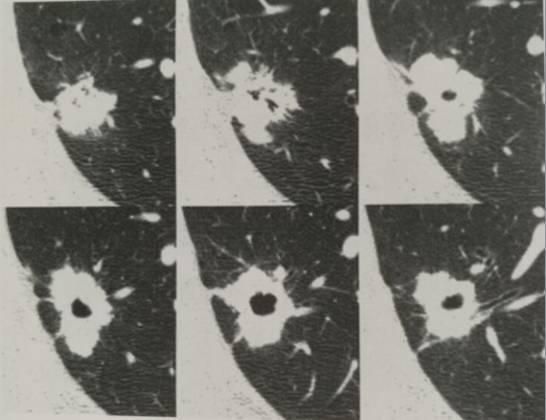

图2

在6个连续HRCT扫描层面显示的空洞型腺癌,结节包含1个不规则的空洞,在形状上不规则,有分叶、锯齿、毛刺、胸膜尾征象,还有几个充气支气管。